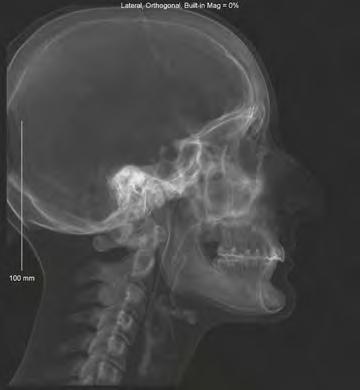

El Dr. Enrique Solano tiene claro, cuando se le pregunta que si al final de su trayectoria profesional le obligaran a quedarse con tan solo tres avances tecnológicos, cuáles escogería. «Uno sería el diagnóstico y planificación en 3D y su flujo digital. Nosotros ya hemos desarrollado con Nemotec (empresa española de gran implantación internacional) la cefalometría MSE en 3D y estamos realmente maravillados de lo que es capaz de aportar. Un segundo avance es lo que aporta el anclaje óseo en el día a día en el tratamiento de Ortodoncia convencional y, sobre todo, en los tratamientos compensatorios de casos complejos, en los que podemos obtener resultados anteriormente cuestionables. En nuestro caso es una rutina el uso de miniplacas como máxima expresión de lo que puede aportar el anclaje óseo, al poder soportar varios vectores de fuerza como sistema compensatorio, en casos que tradicionalmente se consideraban ortognáticos. Un tercer avance sería el de la Ortodoncia plástica con alineadores y la aplicación de la inteligencia artificial (IA) en este campo. Actualmente, nosotros realizamos el seguimiento del tratamiento de nuestros pacientes, monitorizándolos a través del sistema scan-box, que nos permite un control y supervisión de lo obtenido, al superponer las imágenes de la predeterminación del tratamiento con la obtenida, lo que ahorra visitas presenciales en la clínica y reduce el tiempo de sillón.